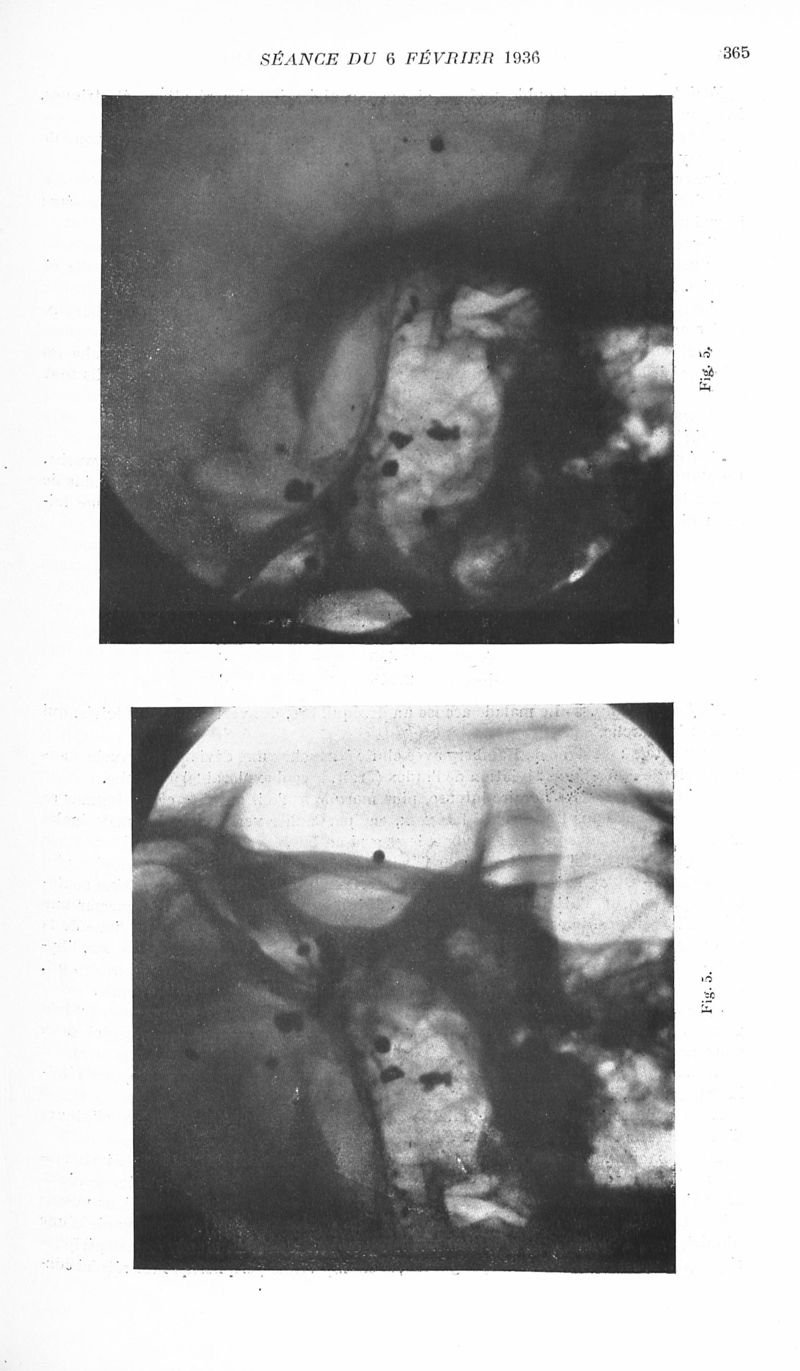

Revue neurologique

1936, vol 1. - Paris : Masson , 1936.